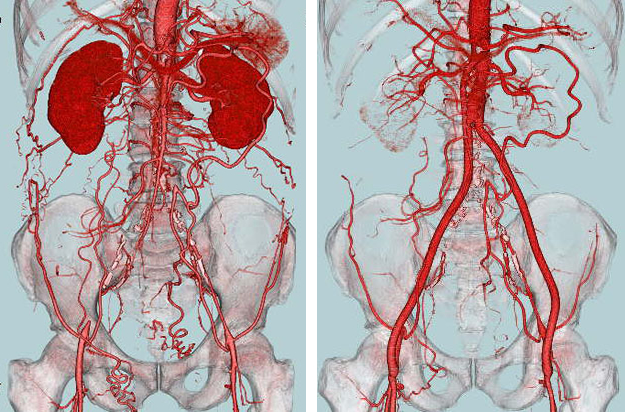

- 大動脈狭窄 【写真】

- 高位大動脈閉塞(Leriche synd) 【写真】

- 腸骨動脈完全閉塞(右) 【写真】

- 腸骨動脈狭窄 【写真】

考え方としては、早期であるほど2の血管内手術のみで治る可能性が高いと考えてよいでしょう。現在の末梢動脈に対する血管内手術の適応は、大動脈・腸骨動脈領域から膝下動脈、さらに足関節から足趾にまで及びます。しかし、それぞれの治療法には当然ながら適応があります。このためしばしば従来からの手術との組み合わせであるハイブリッド手術が必要になりますが、血管内呪術の関与する割合は8~9割にも及んでいます。